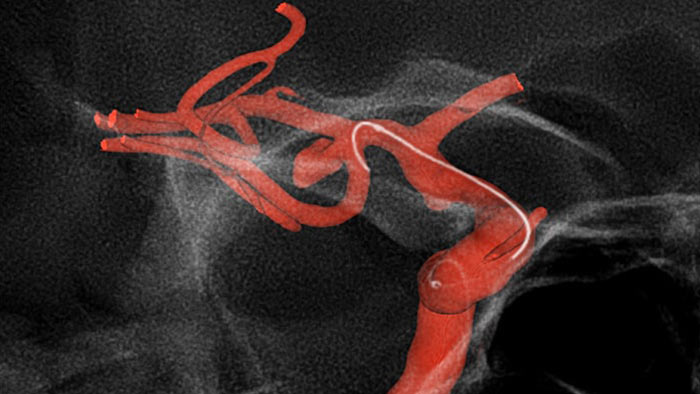

O SmartCT Angio é uma técnica de aquisição de raios X que gera uma visualização 3D completa de alta resolução do sistema vascular cerebral a partir de um único processamento de angiografia rotacional, tudo controlado através do ecrã tátil na mesa. Isto pode melhorar a visibilidade de anatomia tortuosa ou complexa que pode não ser vista numa imagem 2D ou DSA.

O SmartCT Angio proporciona uma vista volumétrica em alguns segundos1 para auxiliar na avaliação da localização, tamanho, pescoço e gravidade do aneurisma para planeamento do tratamento. Os volumes 3D são visualizados com alta resolução espacial e compensação automática do movimento do paciente.